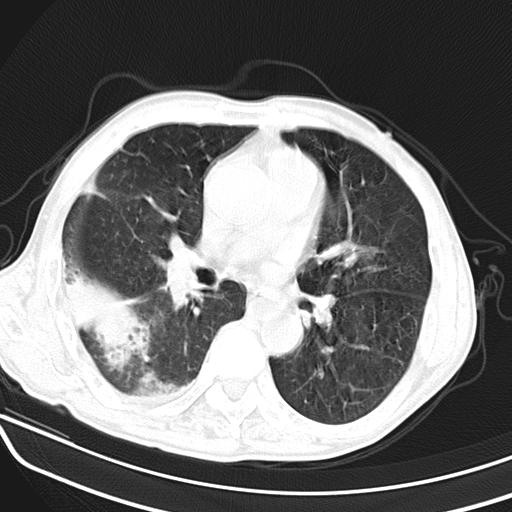

男,70,发烧咳嗽咳痰10余天,查痰结核菌阴性。否认以前有肺病史。治疗10天后症状减轻。 img]/upload/forum/2009/12/302117469692.jpg[/img]

影像所见:右上肺见一巨大厚壁空洞,内壁欠光整,右上肺广泛斑片状、大片状模糊阴影。

影像所见:右上肺见一巨大厚壁空洞,并见分隔,内壁欠光整,右上肺广泛斑片状、大片状磨玻璃阴影。